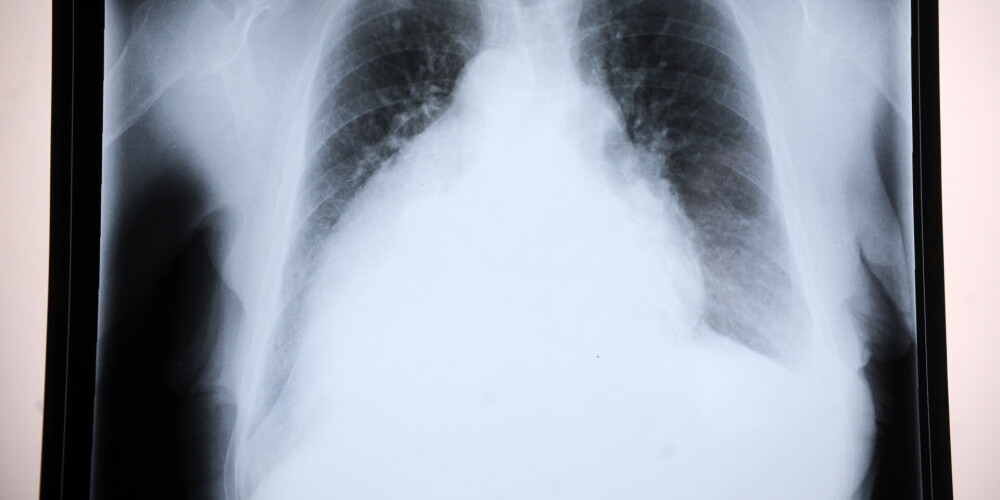

Туберкулез - широко распространённое в мире инфекционное заболевание человека и животных, вызываемое различными видами микобактерий из группы Mycobacterium tuberculosis complex, или иначе палочками Коха. Туберкулез обычно поражает легкие, реже затрагивая другие органы и системы. Mycobacterium tuberculosis передается воздушно-капельным путем при разговоре, кашле и чихании больного. Чаще всего после инфицирования микобактериями заболевание протекает в бессимптомной, скрытой форме, но примерно один из десяти случаев скрытой инфекции, в конце концов, переходит в активную форму. Для человека заболевание является социально зависимым.